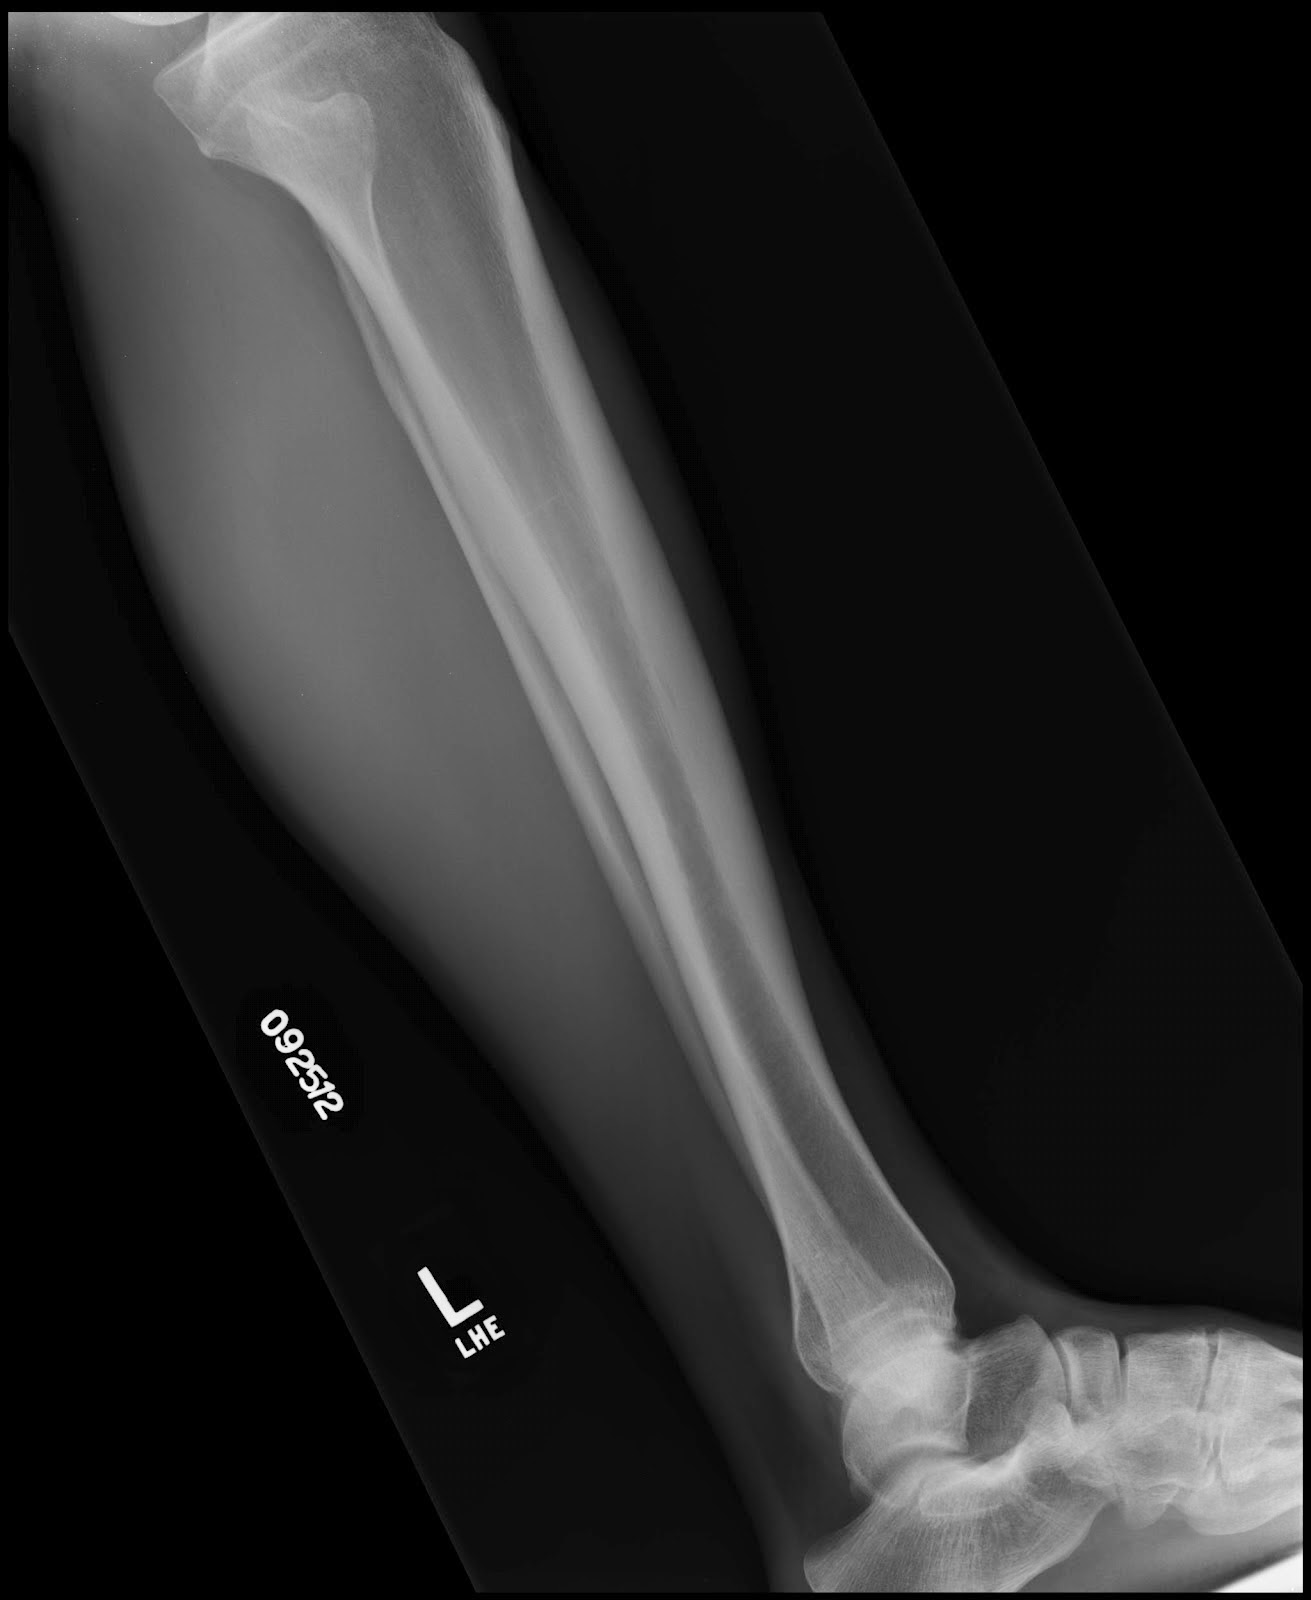

Plain x ray showing a recent fissure fracture at the lower part of a Fissure Fracture X Ray Stress fractures of the tibia result from repeated low force trauma. To determine the severity and treatment/recovery time, doctors will typically perform an. 'toddler's fracture' = tibial spiral fracture in a toddler. It provides an exit route for the chorda tympani from the middle ear to. Tibial fractures usually result from high force trauma. It is necessary when studying the. Fissure Fracture X Ray.

Plain x ray showing a recent fissure fracture at the lower part of a Fissure Fracture X Ray It provides an exit route for the chorda tympani from the middle ear to. It is necessary when studying the x. 'toddler's fracture' = tibial spiral fracture in a toddler. Transverse, oblique and spiral fractures. Stress fractures of the tibia result from repeated low force trauma. Tibial fractures usually result from high force trauma. The petrotympanic fissure (glaserian fissure) can. Fissure Fracture X Ray.